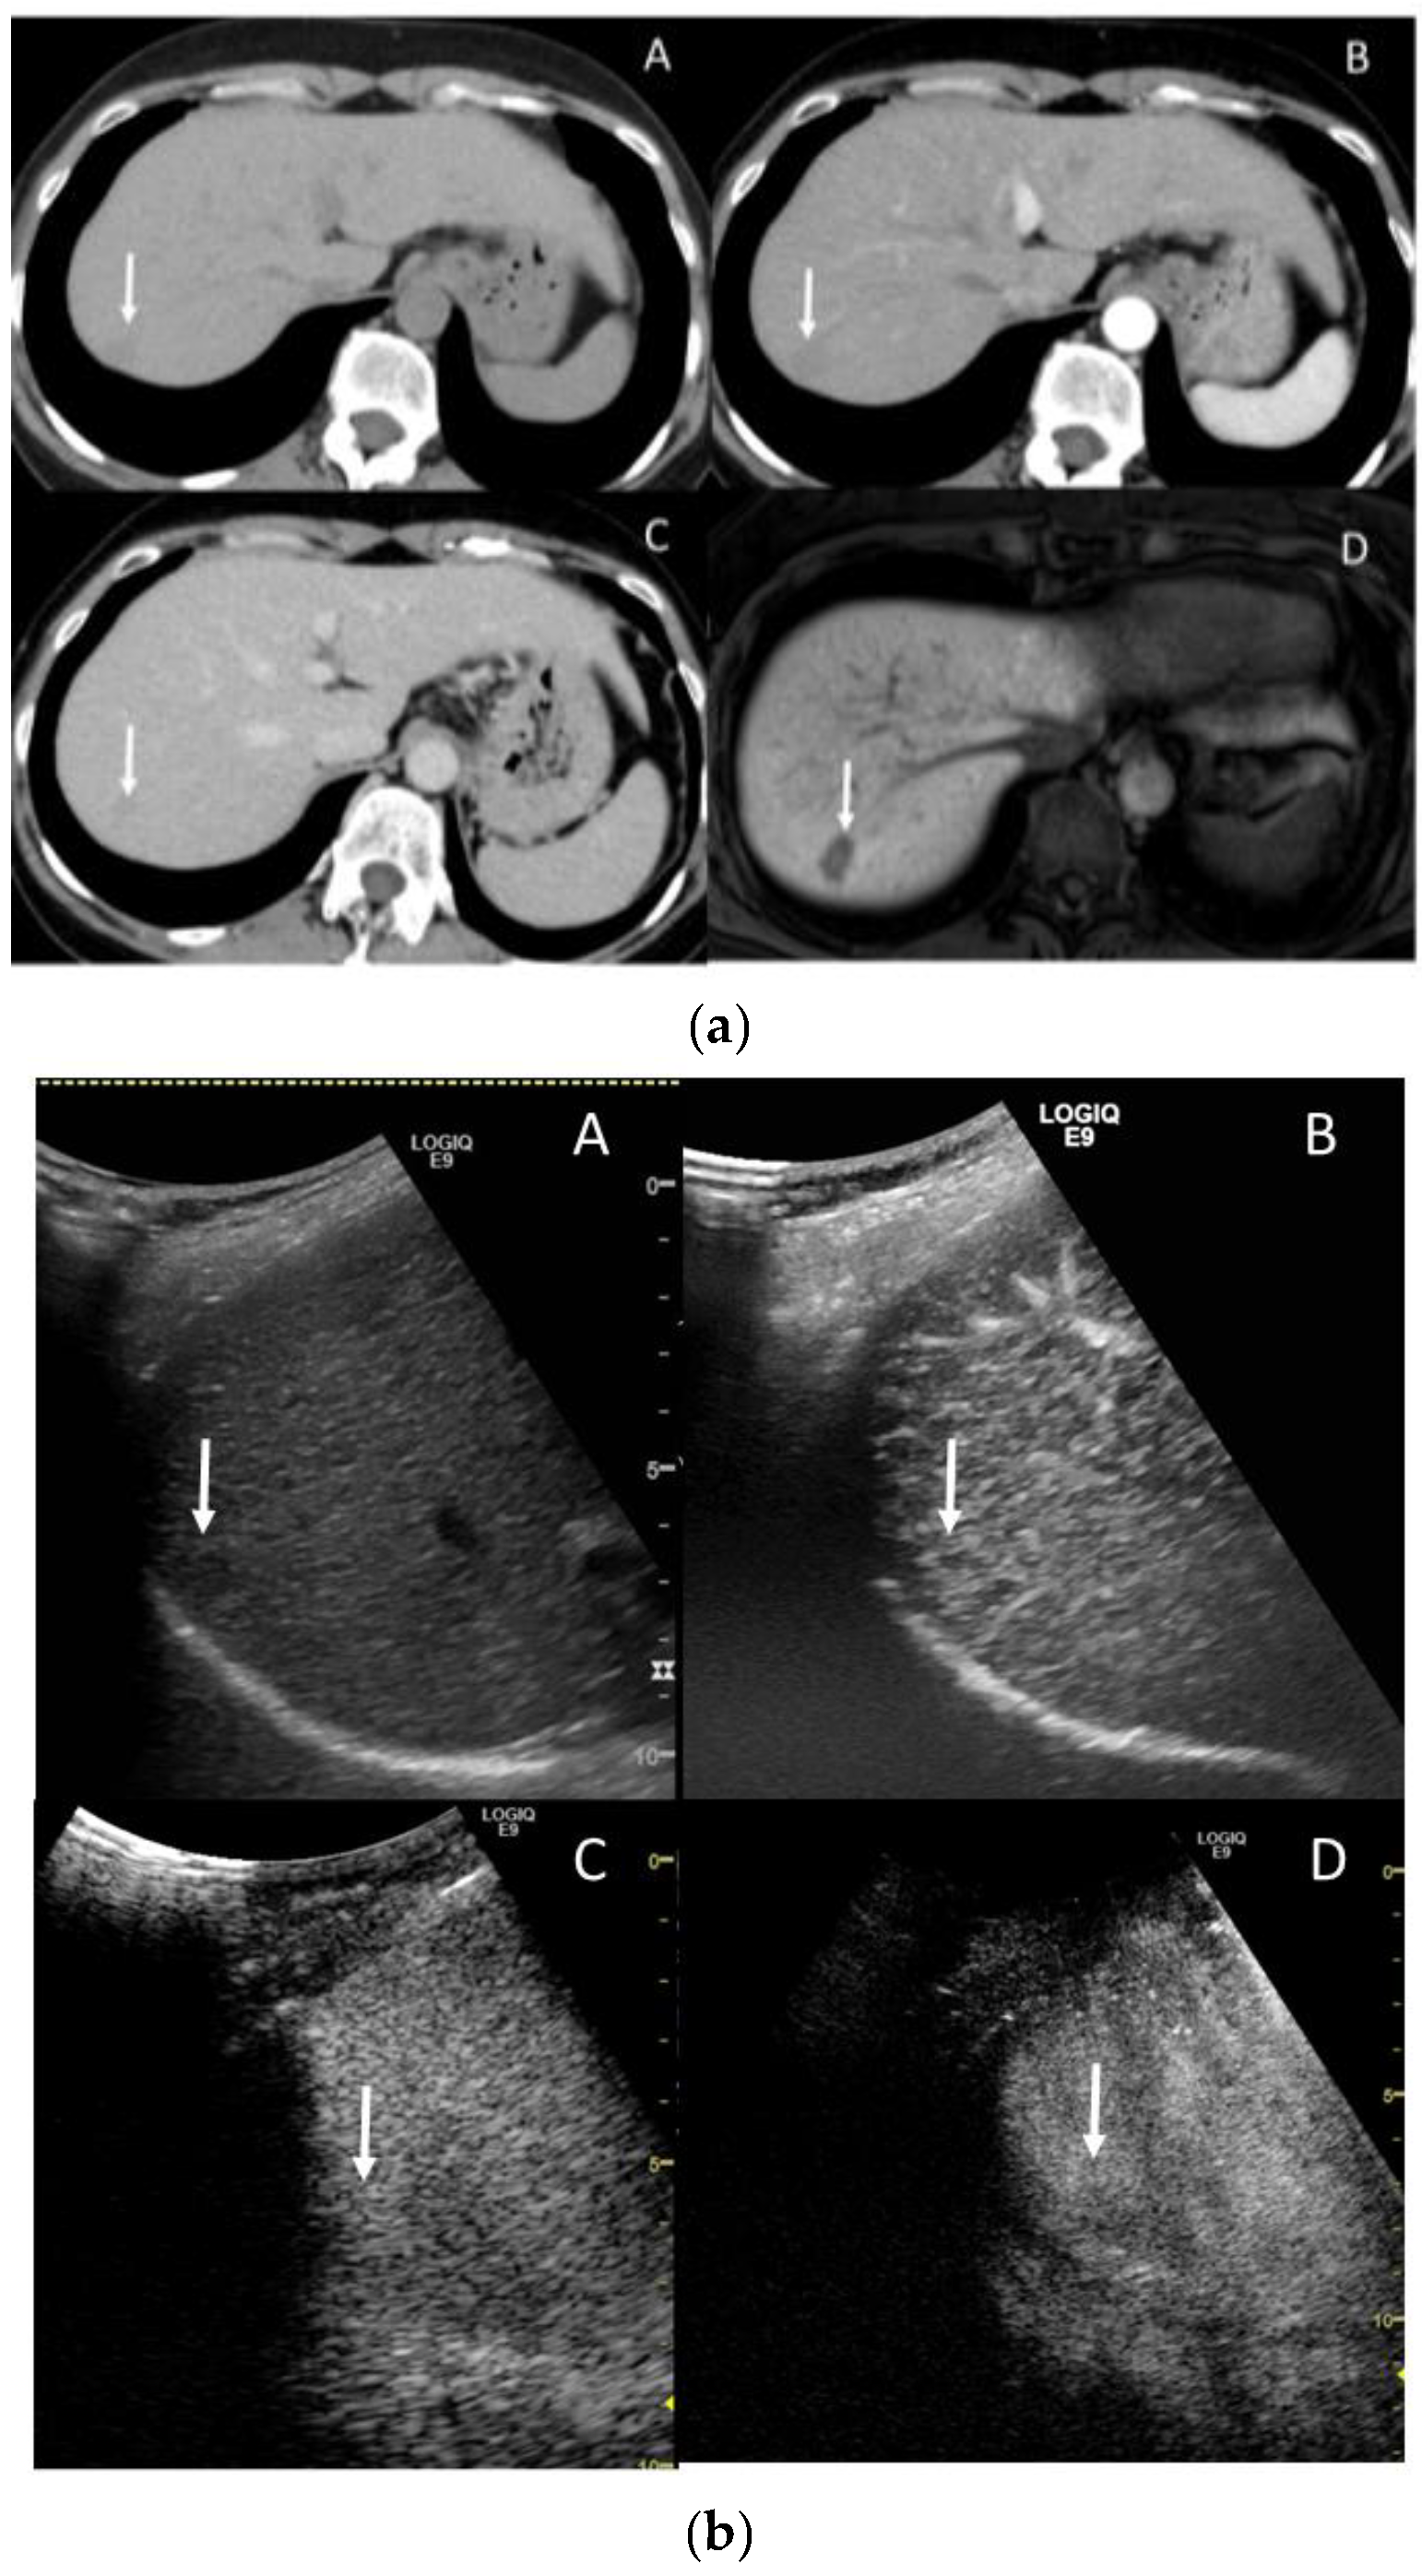

4.2. Early Hepatocellular Carcinoma (Early-HCC)

4.3. Well-Differentiated Hepatocellular Carcinoma (Well-HCC)